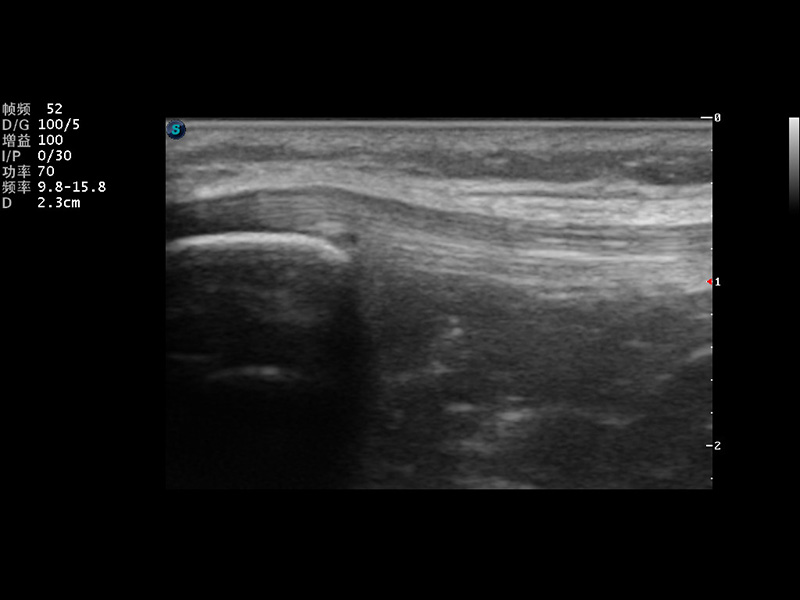

成像技术

μ-Scan微米成像